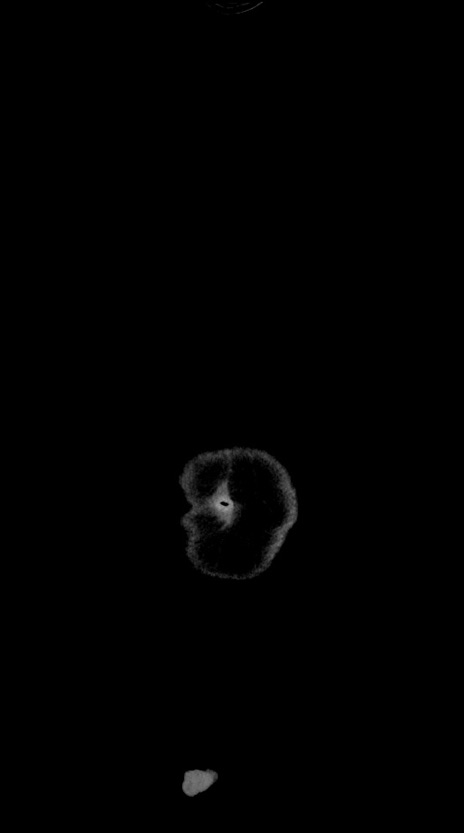

横断像

【症例】60歳代男性

【主訴】嘔吐

【現病歴】胃癌にて胃全摘後。食思不振が悪化し、夜中に嘔吐することがある。

【既往歴】胃癌、胃全摘、脾摘、胆摘後

【データ】WBC 5900、CRP 10.56